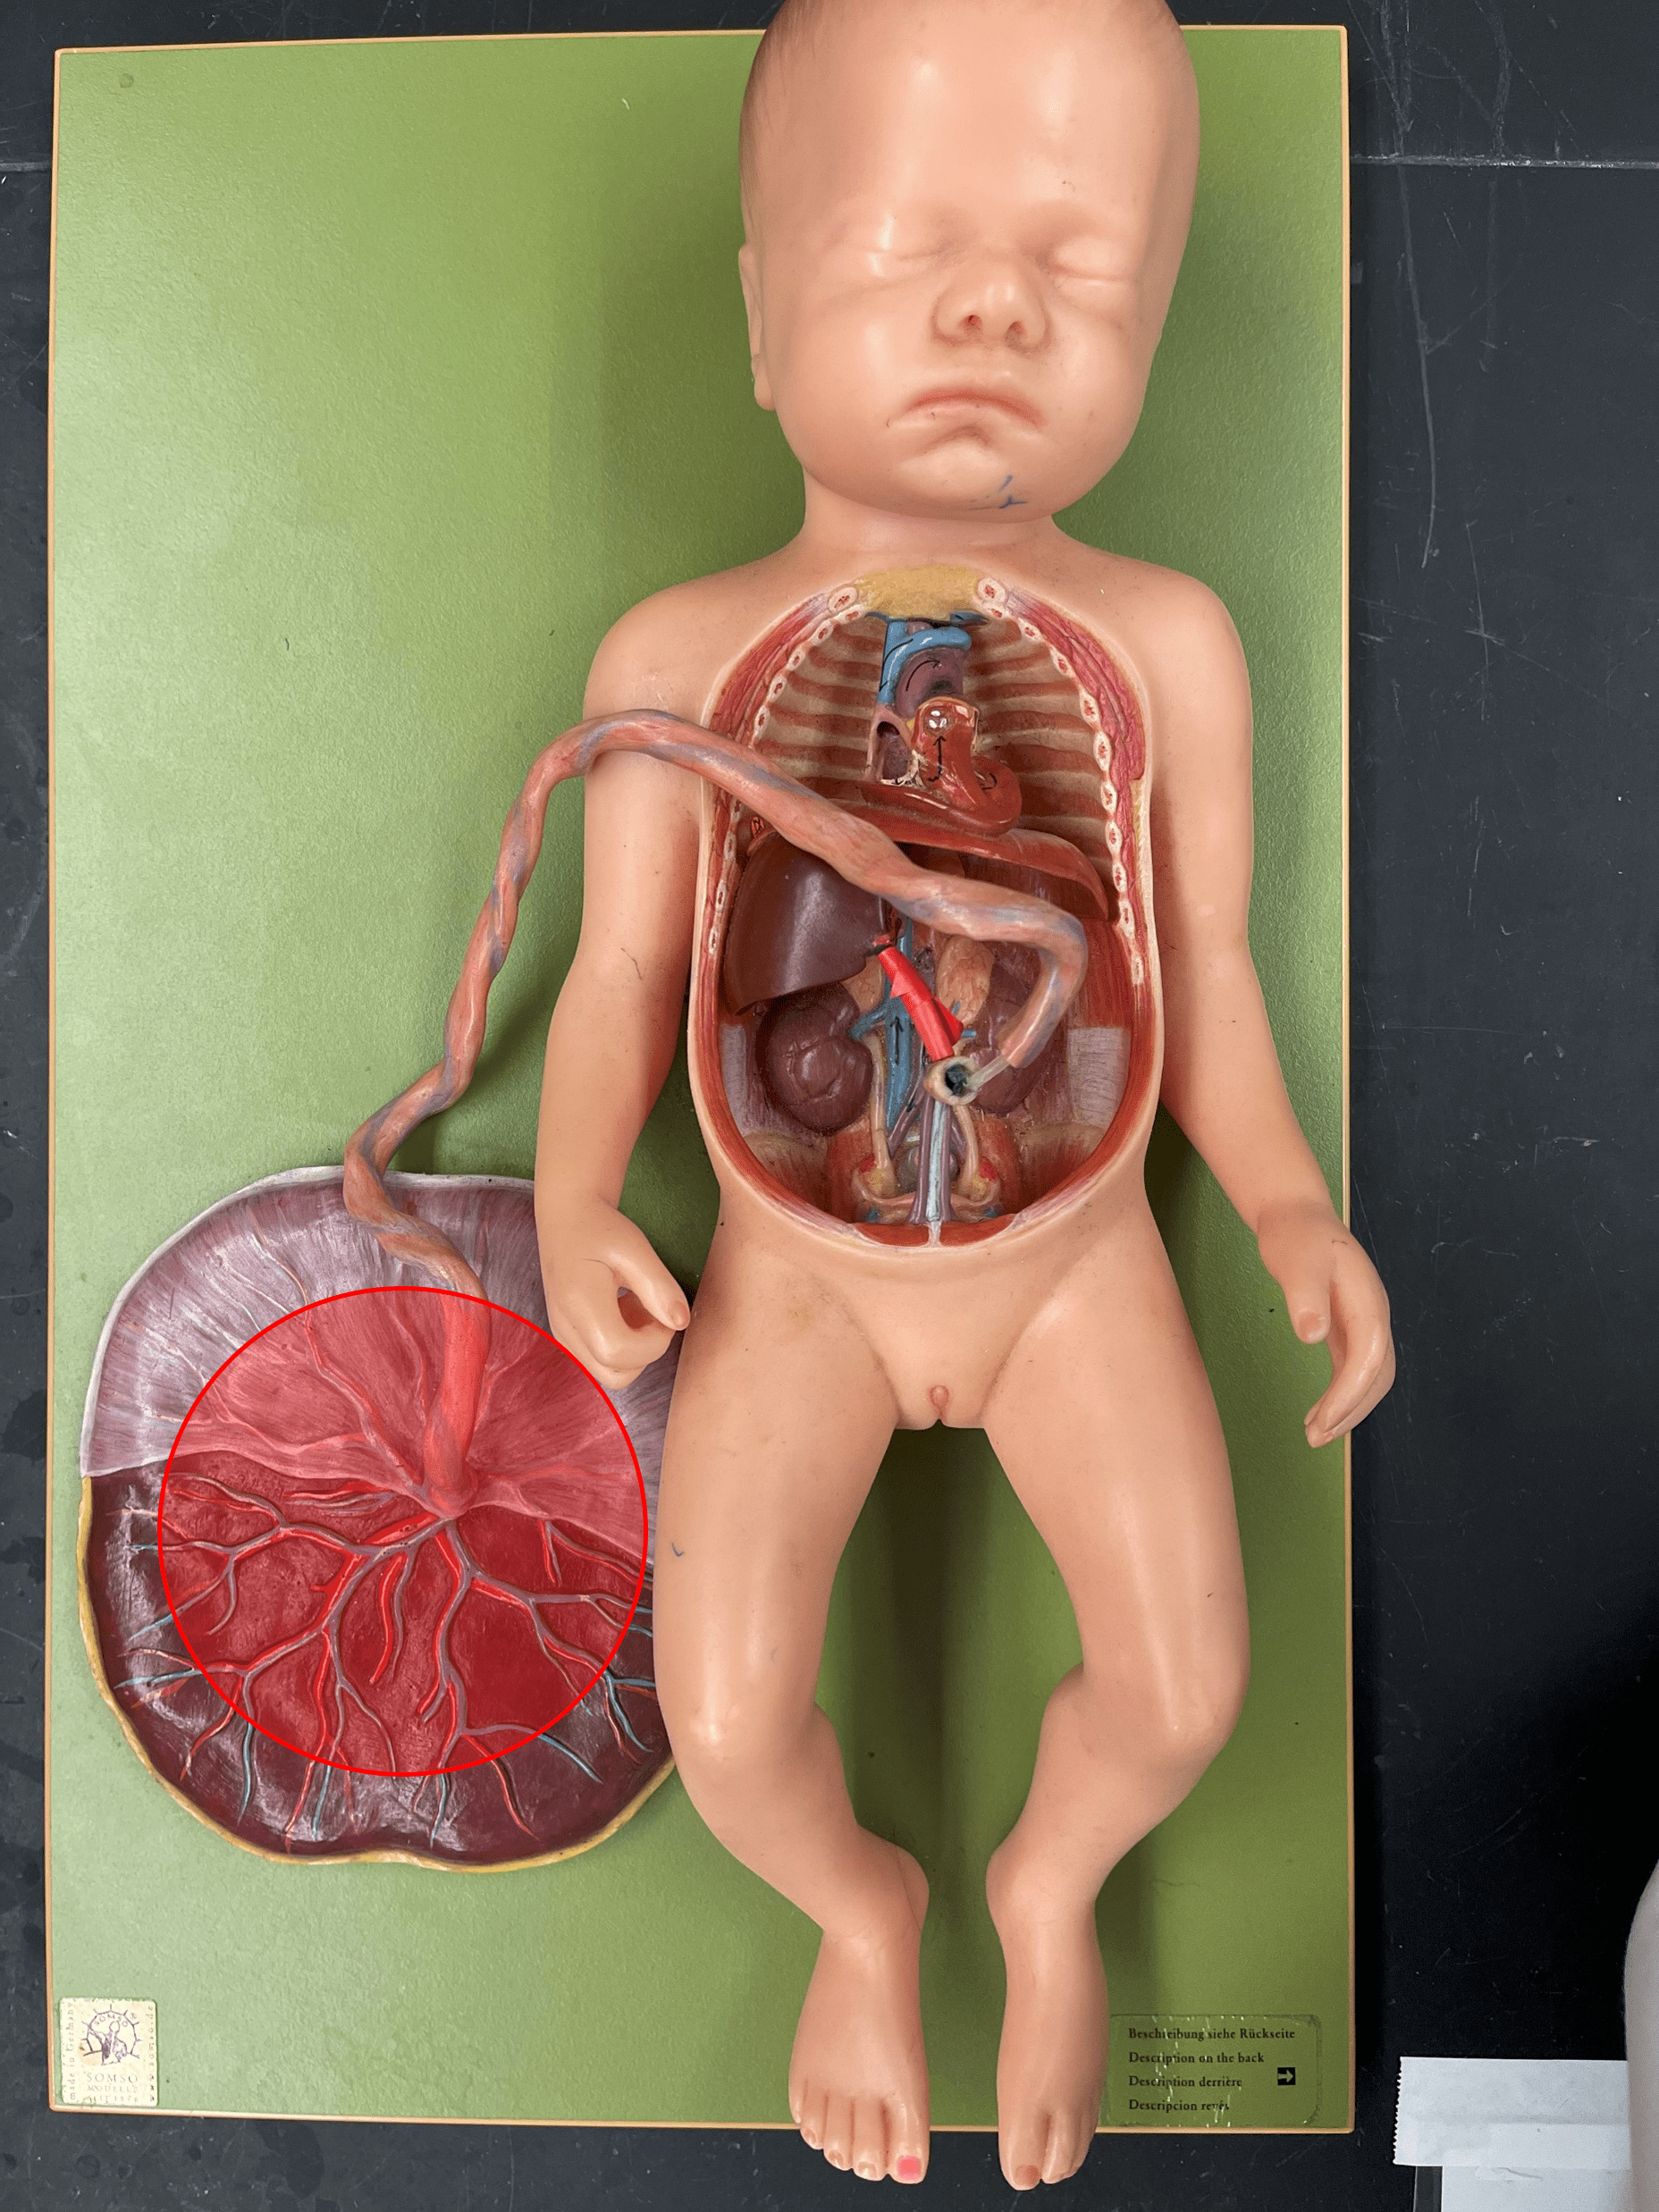

placenta

• Organ that delivers nutrients and oxygen to the fetus and removes wastes from the fetus.

• Connected to the fetus by the umbilical cord.

• Contains chorionic villi from the fetus and intervillous spaces from the mother.

• Connected to the fetus by the umbilical cord.

• Contains chorionic villi from the fetus and intervillous spaces from the mother.

20

New cards

umbilical cord

• Connects the fetus to the placenta.

• Contains an umbilical v. and two umbilical aa. as part of the fetal circulation.

• Contains an umbilical v. and two umbilical aa. as part of the fetal circulation.

21

New cards

ductus venosus

• Part of the fetal circulation.

• Shortcuts blood to the inferior vena cava, bypassing the liver.

• Becomes the ligamentum venosum.

• Shortcuts blood to the inferior vena cava, bypassing the liver.

• Becomes the ligamentum venosum.

22

New cards

foramen ovale

• Part of the fetal circulation.

• Shortcuts blood to the right atrium from the left atrium, bypassing the pulmonary circuit.

• Becomes the fossa ovalis.

• Shortcuts blood to the right atrium from the left atrium, bypassing the pulmonary circuit.

• Becomes the fossa ovalis.

23

New cards

ductus arteriosus

• Part of the fetal circulation.

• Shortcuts blood from the pulmonary trunk to the aorta, bypassing the pulmonary circuit.

• Becomes the ligamentum arteriosum.

• Shortcuts blood from the pulmonary trunk to the aorta, bypassing the pulmonary circuit.

• Becomes the ligamentum arteriosum.